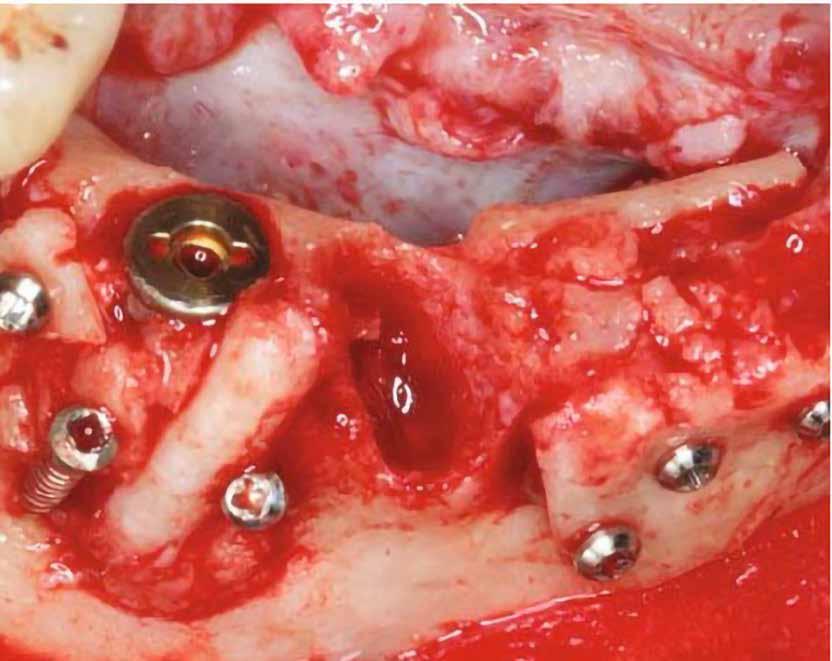

Egy 47 éves páciens jelentkezett nálunk egy alsó, hátsó foghiánnyal, ahol jelentős csontfelszívódást tapasztaltunk a moláris fogak korábbi eltávolítása miatt (1. ábra). Két implantátum körül is volt ínyrecesszió, illetve a keratinizált íny mennyisége minimális volt (kevesebb, mint 1 mm). 4 hónappal az implantációt követően ínykorrekciót végeztünk.

Sebészi technika

Helyi érzéstelenítést végeztünk a műtéti területen artikain és 1:100 000 adrenalin segítségével. A recipiens területet előkészítettük, élesen disszekciót végeztünk, hogy egy izomtapadástól mentes periosteum ágyat képezhessünk. Ettől disztálisan két párhuzamos parakresztális metszést végeztünk egy 15C-s szikepengével, majd a metszéseket egy

2–5. ábra: A metszések és a deepitelizáció. – 6–9. ábra: Félvastag lebeny. – 10. ábra: A nyelezett ínylebeny „bepróbálása”.

horizontális metszéssel kötöttük össze (2–5. ábra). A metszések hosszát és a köztük lévő távolságot minden esetben a lágyszövet augmentációhoz szükséges keratinizált szövet határozza meg. A lebeny deepitelizációját egy 15C-s szikepengével végeztük (6. ábra). Ezt követően félvastag lebenyt preparáltunk (7. ábra). A lebenyt apikálisan, az alapjáról belső, felületes metszéssel felszabadítottuk, hogy passzívan áthelyezhessük és rögzíthessük, feszülés nélkül. Meziális irányba 180 fokkal átforgattuk (8–9. ábra). A meziális papillát alagúttechnikával (tunnelling technique) készítettük elő a graft befogadására (10. ábra). Az így kialakított lebenyt a recipiens ágyban rögzítettük az újonnan kialakított vesztibulum alapjánál 5-0 nem felszívódó PTFE (Coreflon, IMPLACORE) varratokkal. A graftot behajtottuk az ínyszél alá és meziális oldalon rögzítettük PTFE varratokkal (11–14. ábra) A műtétet követően napi kétszeri, 0,12%-os klórhexidin tartalmú szájvízzel történő öblögetést javasoltunk a páciensnek, két héten keresztül. Gyulladáscsökkentésre 8 óránként 400 mg Ibuprofént javasoltunk, három napon keresztül. A páciens elmondása szerint sem fájdalmat, sem különösebb diszkomfortot nem tapasztalt. Ezt követően, további 4 héten keresztül, 0,2%-os klórhexidin tartalmú szájvízzel történő öblögetést javasoltunk a betegnek és instruáltuk, hogy lehetőleg ne mossa fogkefével az érintett területet. A varratokat egy héttel később távolítottuk el. A donor és a recipiens terület – 10 nappal a műtétet követően – kiválóan gyógyult (15–16. ábra). Az ezt követő kontrollokat a következő időpontokban ejtettük meg: kettő, illetve négy héttel a műtét után, majd három, hat és tizenkét hónappal később, ezt követően pedig félévente (17–20. ábra). Minden kontroll alkalmával professzionális fenntartó kezelést végeztünk a területen.